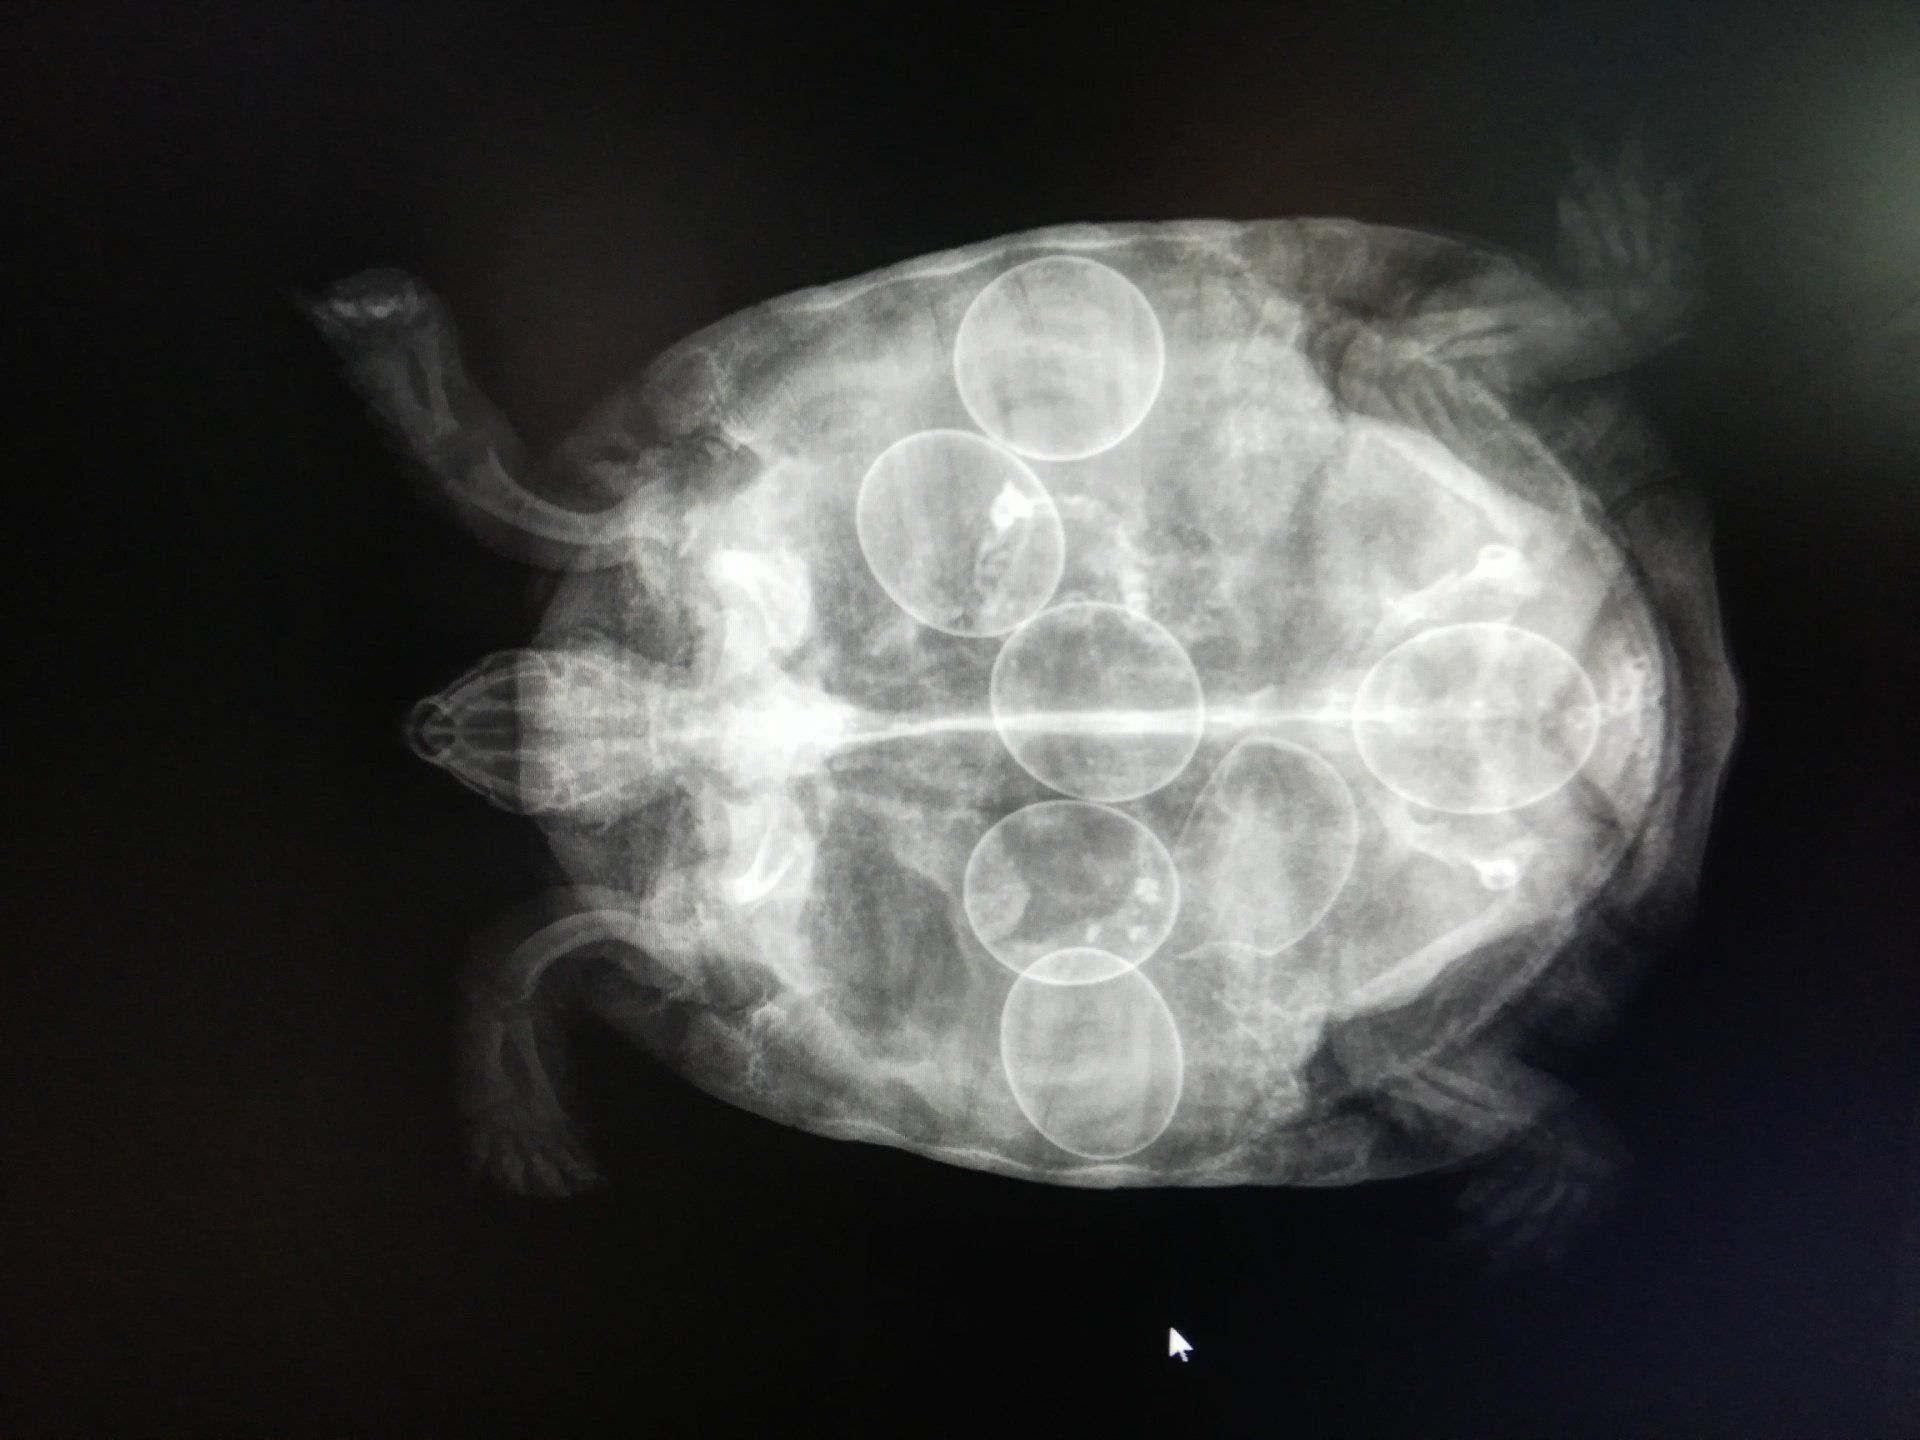

Radiographie abdominale:

Pour la recherche de pathologies concernant les organes abdominaux (foie, reins, rate, appareil digestif…)